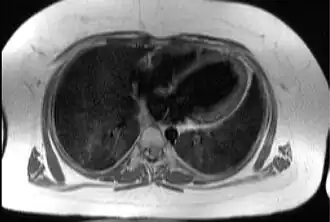

Трансаксиальное изображение грудной клетки на уровне сердца, иллюстрирующее типичную жировую ткань подкожно и эпикардиально у пациента с синдромом Альстрёма. | |